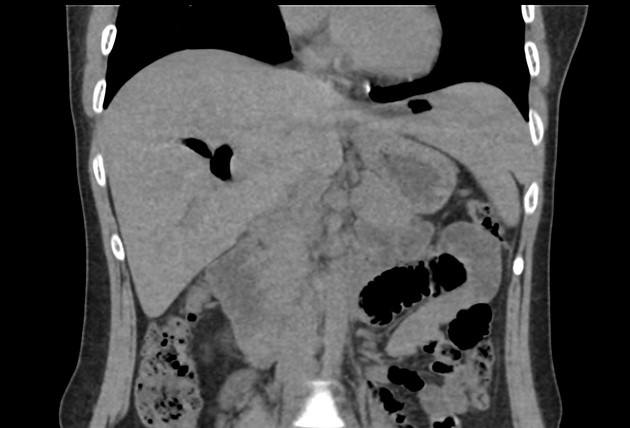

Khí đường mật

Khí đường mật - Ảnh 4

» Thông tin: Nữ giới – 30 tuổi.

» Lâm sàng: Đau mạn sườn phải / Tiền sử cắt túi mật.